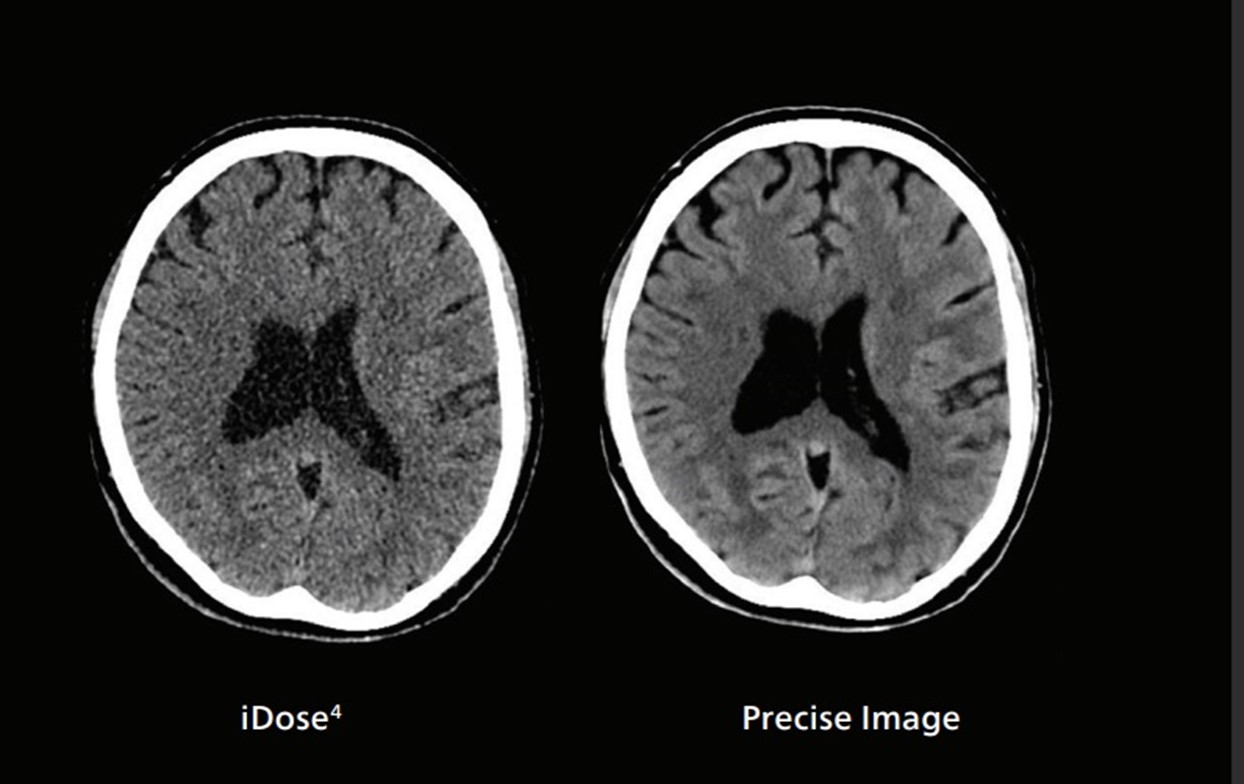

De to CT-bildene er tatt med samme stråledose. Her kan man tydelig se at det høyre bildet som er tatt av CT med avansert KI programvare, er et mye klarere bilde enn det som kommer fra en CT uten tilsvarende programvare. Illustrasjonsbilde: Philips.

Denne CT-maskinen inneholder en nyere teknologi som benytter kunstig intelligens (KI), både for bilderekonstruksjon og for kameraposisjonering av pasienten.

Den avanserte programvaren i CT-maskinen er trent opp til å gjenkjenne og skille mellom signal fra ulike vevstyper ved hjelp av kunstig intelligens.

- Dette gir maskinen evnen til å fjerne støy i bildene og dermed forbedre bildekvaliteten betraktelig. Det gir oss mulighet til å utføre undersøkelser med lavere stråledoser uten at det går på bekostning av bildekvaliteten. Dette er spesielt viktig for kreftpasienter som ofte er til regelmessige CT-undersøkelser, sier fagradiograf CT, Ali Salahi.